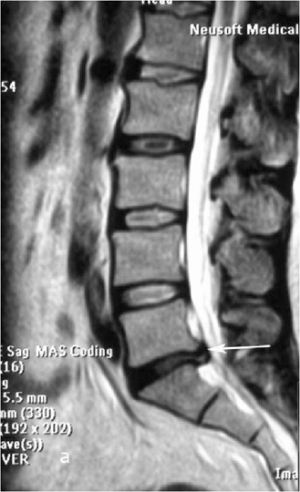

При рентгенографии (Рис.7) и МРТ (Рис.8) поясничного отдела позвоночника выявляется дегенеративный ретролистез L5 позвонка, секвестрированная  парамедианная грыжа мп диска L5-S1  слева.

Рис. 9a. Магнитно-резонансная томография (МРТ) поясничного отдела позвоночника в сагиттальной (a) и аксиальной  (b) проекции. Стрелкой показана мп секвестрированная парамедианная грыжа диска L5-S1 слева. Рис. 9b. Магнитно-резонансная томография (МРТ) поясничного отдела позвоночника в сагиттальной (a) и аксиальной  (b) проекции. Стрелкой показана мп секвестрированная парамедианная грыжа диска L5-S1 слева.

Рис. 8a,b. Магнитно-резонансная томография (МРТ) поясничного отдела позвоночника в сагиттальной (a) и аксиальной (b) проекции. Стрелкой показана мп секвестрированная парамедианная грыжа диска L5-S1 слева.